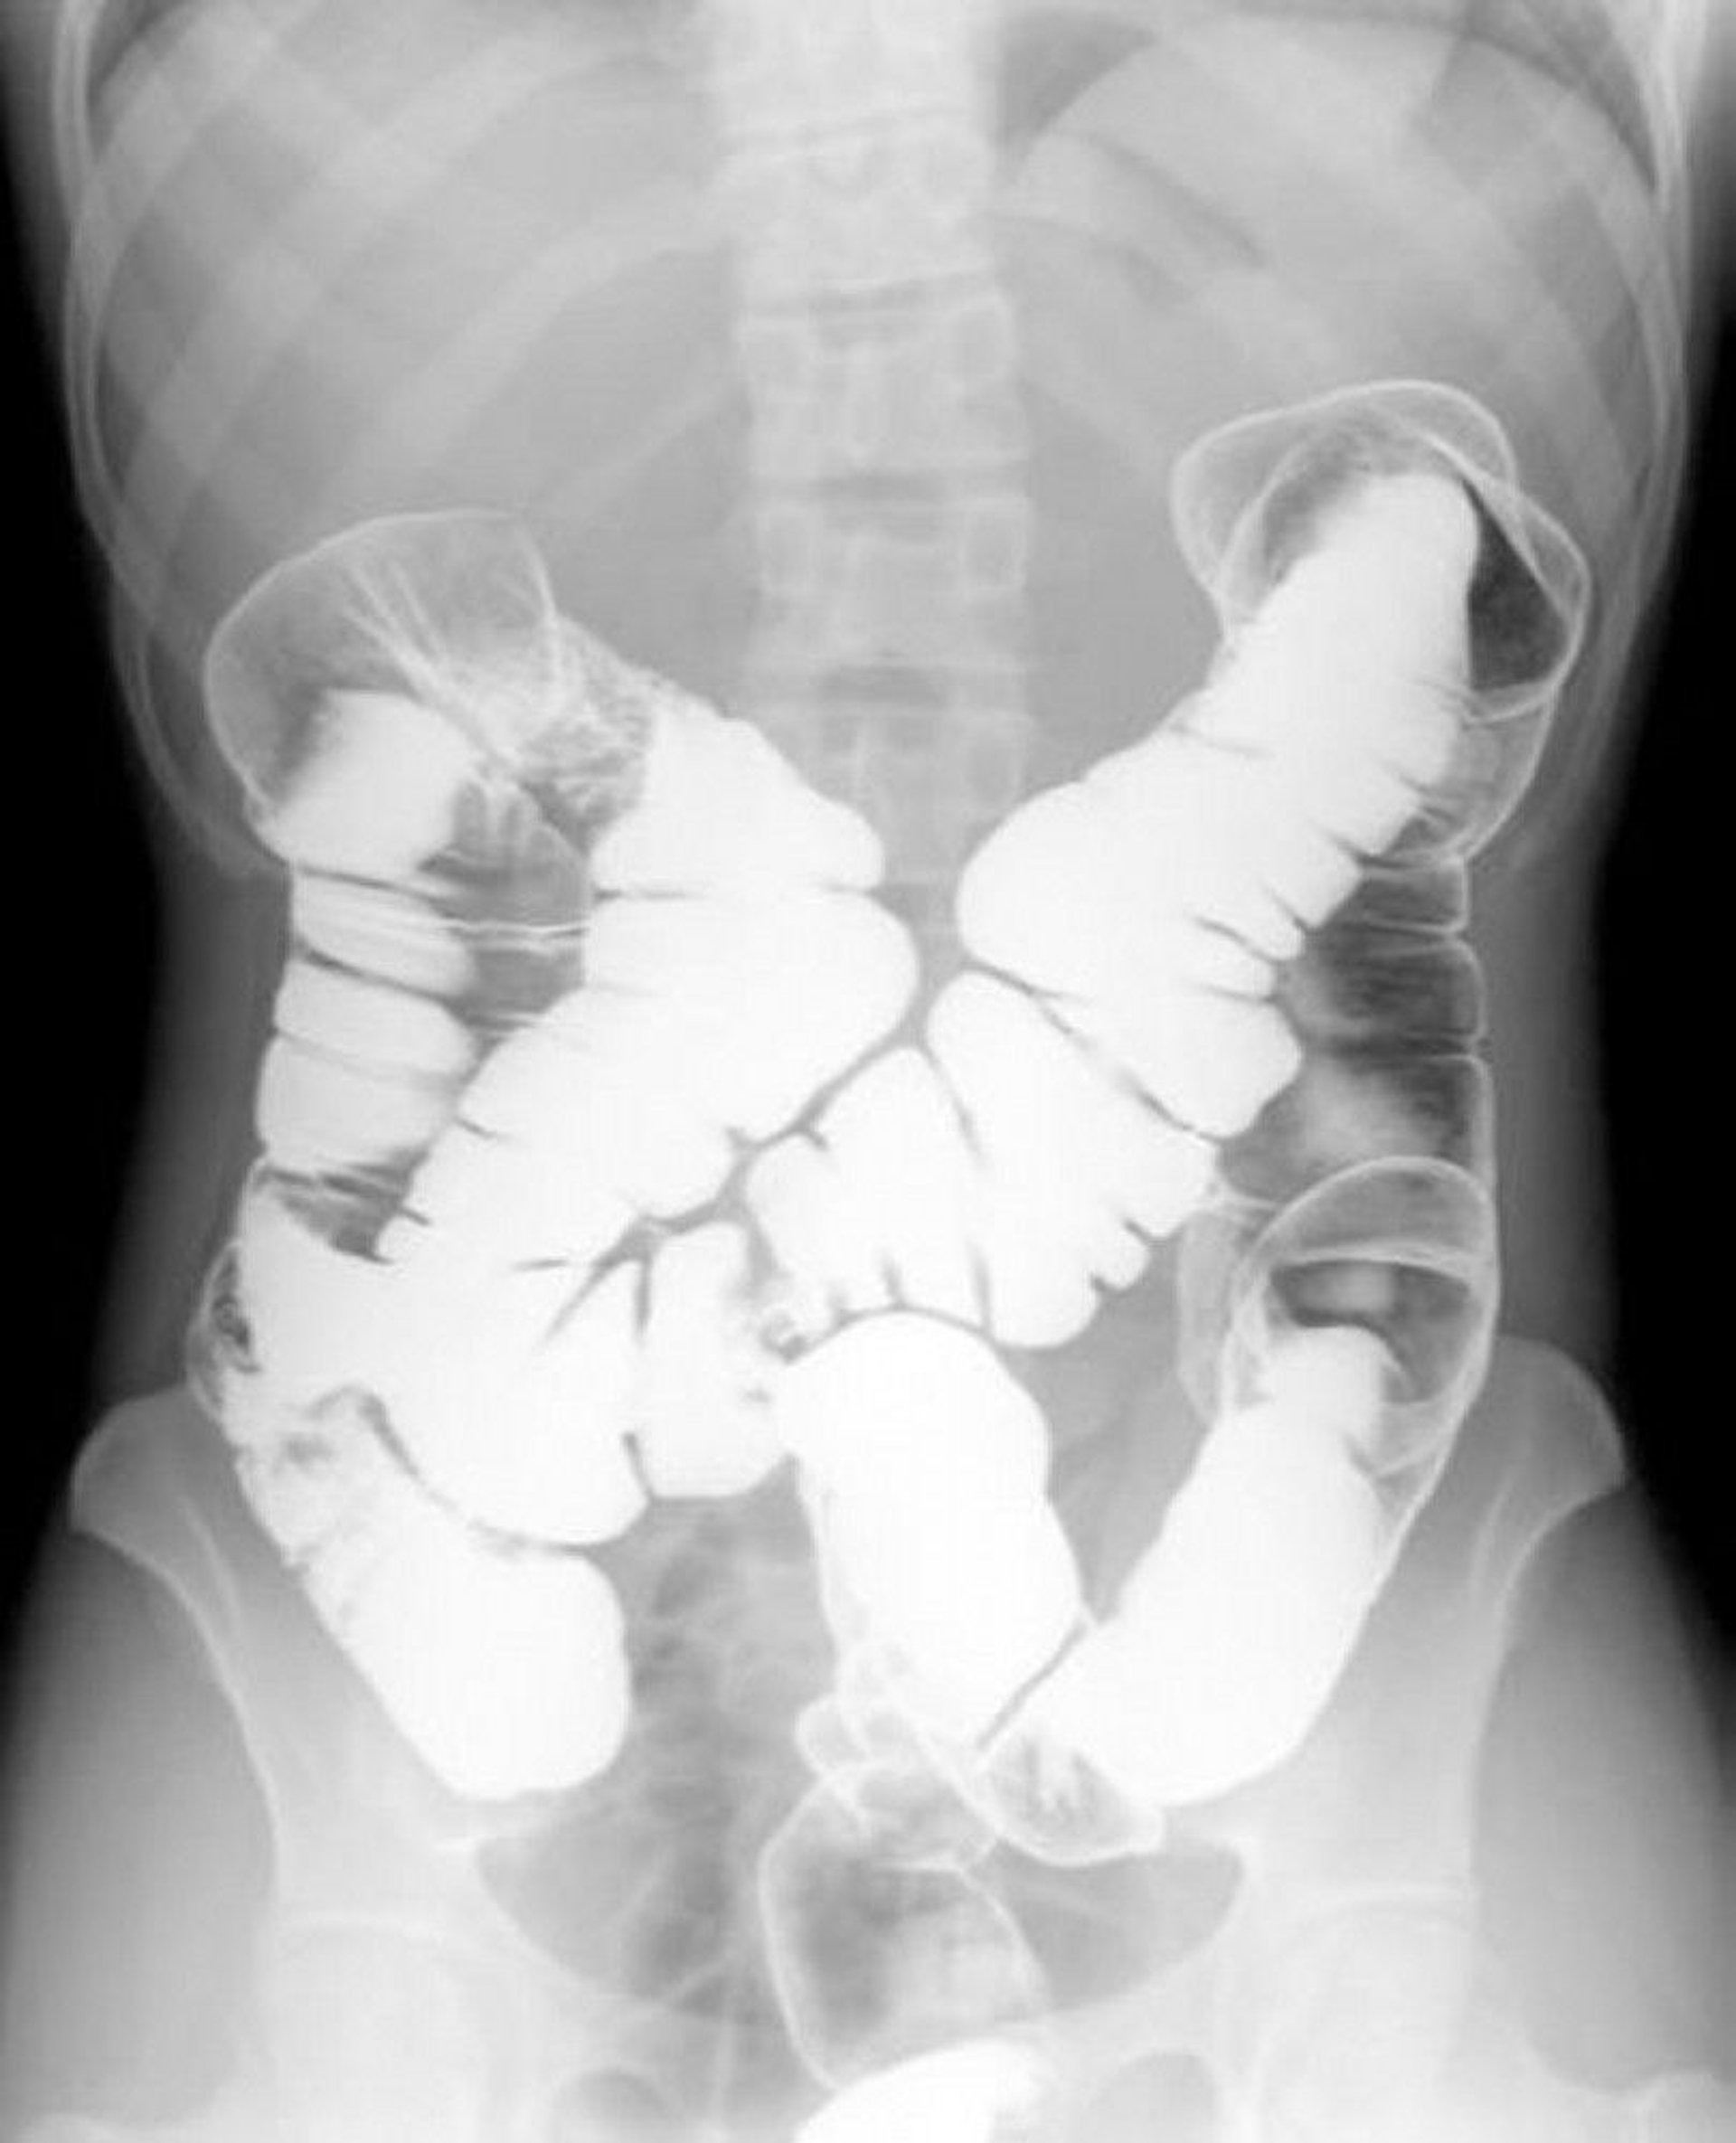

ImageDoubleContrast Barium Enema Showing Normal AnatomyMerck Manual Coffee Enema Merck Manual The number one reason people use coffee enemas is for detoxifying the liver. More recently, directions for administration of various types of enemas, including coffee enemas, were included in medical and nursing textbooks. Why would i want to put coffee there? Coffee enemas are frequently used in natural cancer protocols such as the gerson therapy (www.gerson.org). Until 1977, the coffee. Coffee Enema Merck Manual.